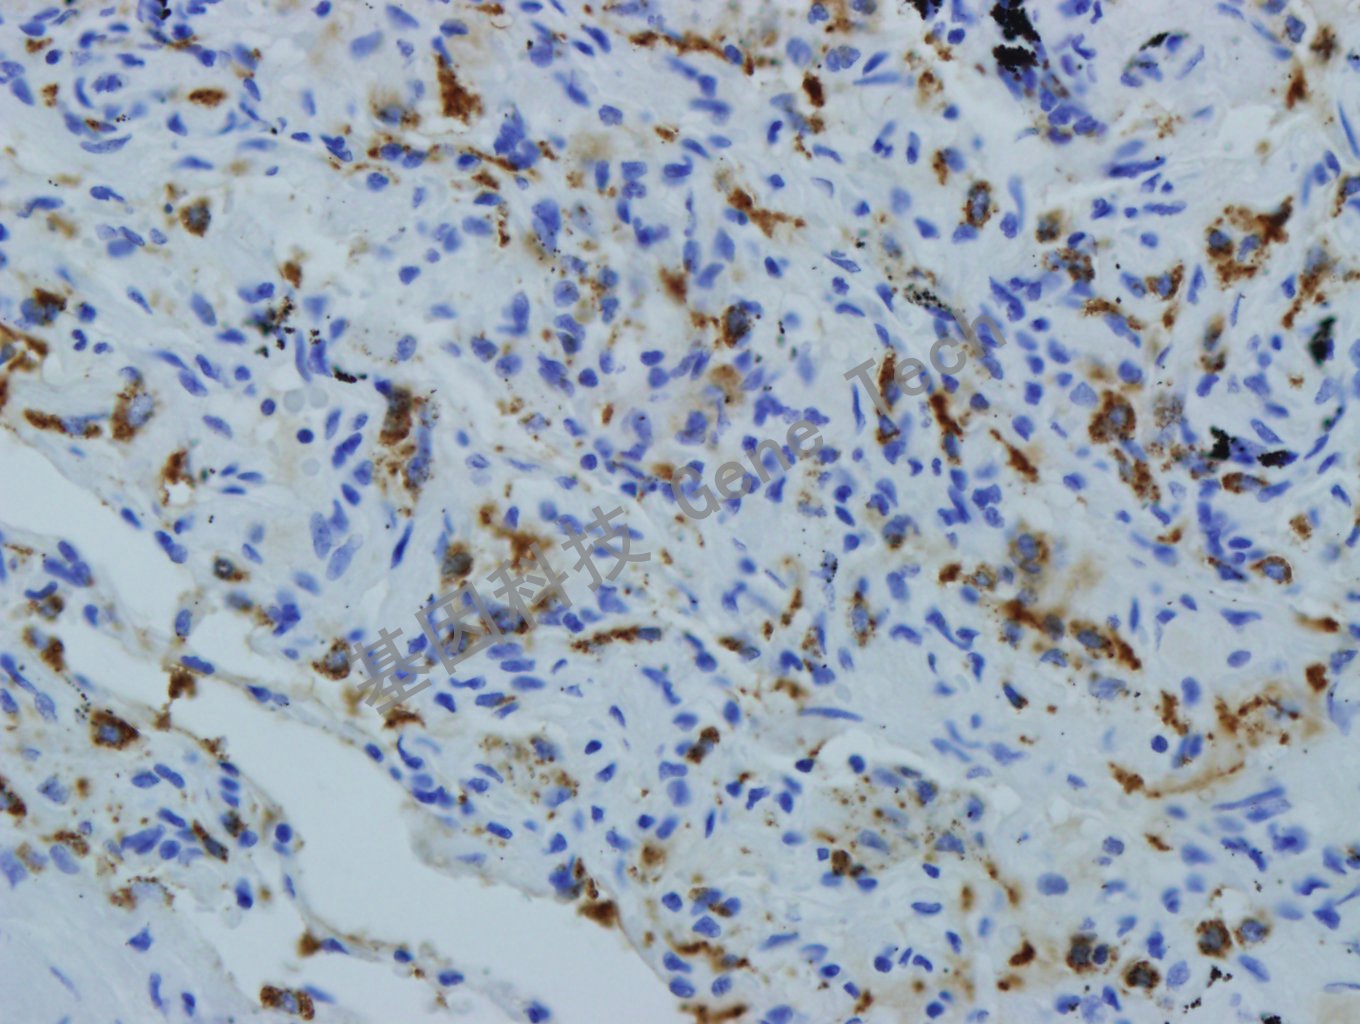

| 肺癌石蠟切片,用 SP-B(GT2277)染色,細(xì)胞漿陽(yáng)性,DAB 顯色。 | ||

| 預(yù)處理:高pH熱修復(fù) | 陽(yáng)性部位:細(xì)胞漿 | 陽(yáng)性對(duì)照:肺癌 |

| 簡(jiǎn)介:SP-B(Surfactant protenin B, 肺表面活性蛋白B)肺的表面活性復(fù)合物的抗原決定簇之一。主要表達(dá)于分化程度較高的肺II型肺泡上皮細(xì)胞核具有Calar細(xì)胞分化特征的腺癌,在低分化的肺腺癌中常常不表達(dá),在肺鱗癌、大細(xì)胞癌和非肺原發(fā)性腺癌中陰性。聯(lián)合TTF-1用于肺癌的輔助診斷以及肺腺癌與轉(zhuǎn)移性腺癌的鑒別診斷。 | ||